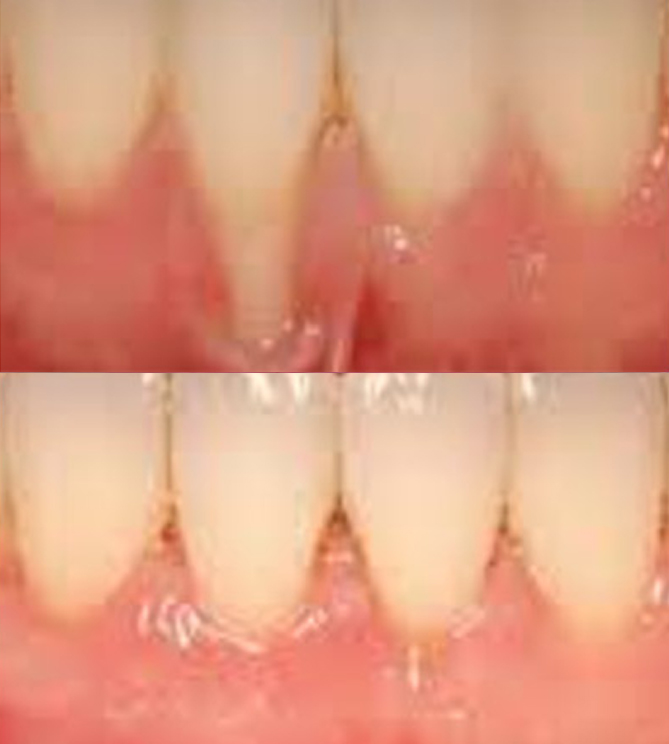

전후사진